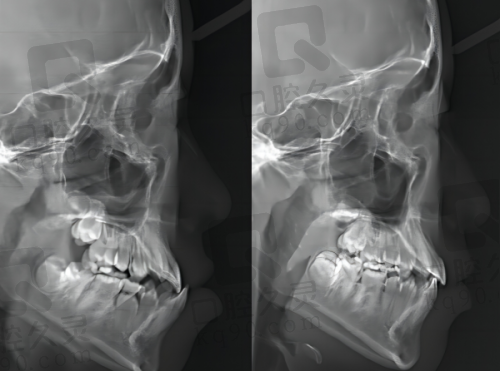

牙齿矫正也是医院的特色项目之一。医院拥有多种矫正方式,如传统金属矫正、陶瓷矫正、隐形矫正等。医生会根据患者的牙齿畸形程度和个人需求,制定更适合的矫正方案,帮助患者拥有整齐美观的牙齿。

在治疗成效方面,不少患者通过在医院的治疗,牙齿问题得到了有效解决。比如,一些牙齿缺失的患者通过种植牙修复了正常的咀嚼功能;牙齿不齐的患者通过矫正拥有了整齐的牙齿。这些患者都对医院的技术和医生的专精水平给予了高度评价。